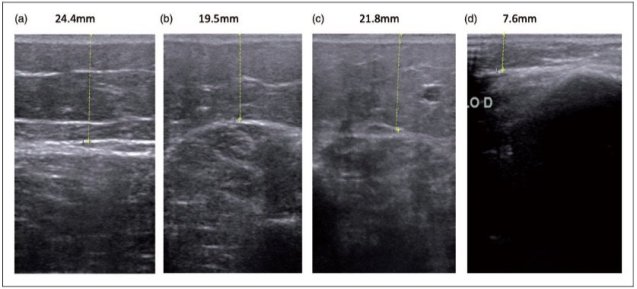

Lipödemde ultrasonografik değerlendirme

Lipödemde bacaklarda ödem sıvısı görülmez, ancak kalın yağ dokusu tabakası görülmektedir. Cilt dokusu ve kas arasındaki bölgede yeralan yağ dokusu ileri derecede kalınlaşır. Normal bireyler ile karşılaştırıldığında yaklaşık 2-3 misli yağ dokusu artışı saptanır.

Resim. Ultrasonda ciltaltı yağ dokusu kalınlığında artış

Bu hastalarda yapılan Dopper ultrasonda derin ve yüzeyel toplardamarlar normal olarak izlenir. Bacak ön yüzünden yapılan ölçümlerde cilt kalınlığı ortalama 21-22,5 mm arasında değişmektedir.